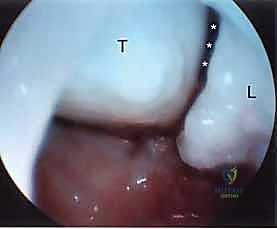

1. The Midcarpal Radial Portal (MCR)

- Location: Approximately 1 cm distal to the 3-4 portal. It is bounded radially by the ECRB tendon and ulnarly by the EDC tendons.

- Anatomy: This portal enters the midcarpal joint, providing a view of the scaphoid, lunate, capitate, and hamate articulations.

- Neurovascular Risks: Generally safe, but the superficial radial nerve branches can be in the vicinity more radially.

- Function: A primary viewing portal for midcarpal arthroscopy, allowing triangulation with the midcarpal ulnar portal for instrumentation. Essential for probing the SLIL and LTIL joint spaces for instability and assessing chondral lesions.